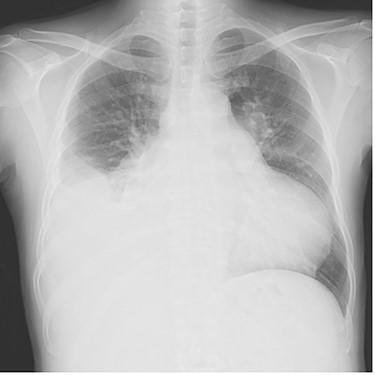

Chest radiography showed an enlarged heart with a cardiothoracic ratio of 73% and right pleural effusion (Fig. 1). Laboratory test results were as follows: blood urea nitrogen, 48.1 mg/dl; creatinine, 1.96 mg/dl; total bilirubin, 2.7 mg/dl and N-terminal prohormone of brain natriuretic peptide: 3043 pg/ml. Transthoracic echocardiography revealed ejection fraction of 49%, severe AR, mild to moderate mitral regurgitation, severe pulmonary regurgitation and mild to moderate tricuspid regurgitation. The pulmonary valve’s maximum pressure gradient had decreased from 31 mmHg 8 months previously to 5 mmHg. The diameter of the ascending aorta was 39.2 mm, sinotubular junction was 36.1 mm and Valsalva sinus was 47.4 mm. Cardiac catheterization showed no significant coronary artery stenosis.

Intraoperative photograph; (A) The remnants of the pulmonary valve; (B, C). pulmonary valve replacement and patching.